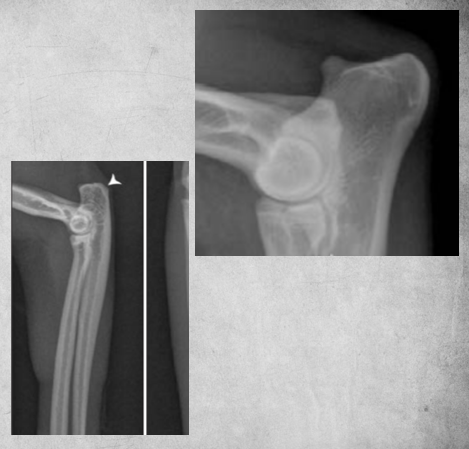

Describe Premature closure of growth plate.

e.g. distal ulna such as in image

results in growth discrepancy and may disrupt the function of the joint

What does this depict?

Premature closure of growth plate distal radius.